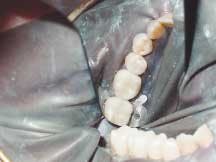

The patient presented with the mesial marginal ridge of Tooth No. 31 fractured, and the distal marginal ridge of Tooth No. 30 fractured. Secondary decay was present around the tarnished and worn amalgams in Teeth Nos. 29 through 31 (Figure 1). Following the placement of a rubber dam, the amalgam restorations and carious tissues were removed. The teeth were then prepared to proper cavity form for the placement of ceramic onlays. Next, the teeth were powdered with an optical contrasting agent (Vita) (Figure 2). A series of optical impression images were taken to record the entire lower right quadrant in the same impression (Figure 3).